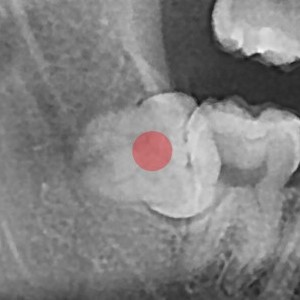

사랑니발치 10대/여성

5e20e086184bc11a2d853605b7813944_1764319801_2575.jpg